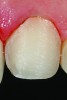

CL-I

CL-I is the purest form of no-preparation or practically prep-less veneers, but can include a discreet finish line or only a loupes-detectable margin (Figure 1). The term addition veneers frequently describes this preparation design today. In this classification, 95% to 100% of enamel volume remains after preparation, and no dentin is exposed. Ideal whenever possible, preparation must be completely and only in enamel.

Fig 2. Photograph of a no-preparation to practically preparationless Class I veneer preparation.

Figure 2